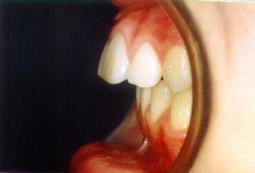

Zahnfehlstellung

Tiefbiss (tiefer Biss)

Die oberen Schneidezähne überlappen die unteren

Schneidezähne mehr als 3 mm und man sieht die unteren

Schneidezähne kaum noch [24].

Beim Tiefbiss überdecken die oberen Schneidezähne

die unteren Schneidezähne fast komplett.

Man sieht die unteren Schneidezähne kaum noch (Foto

von Praxis Dr. Kuster).